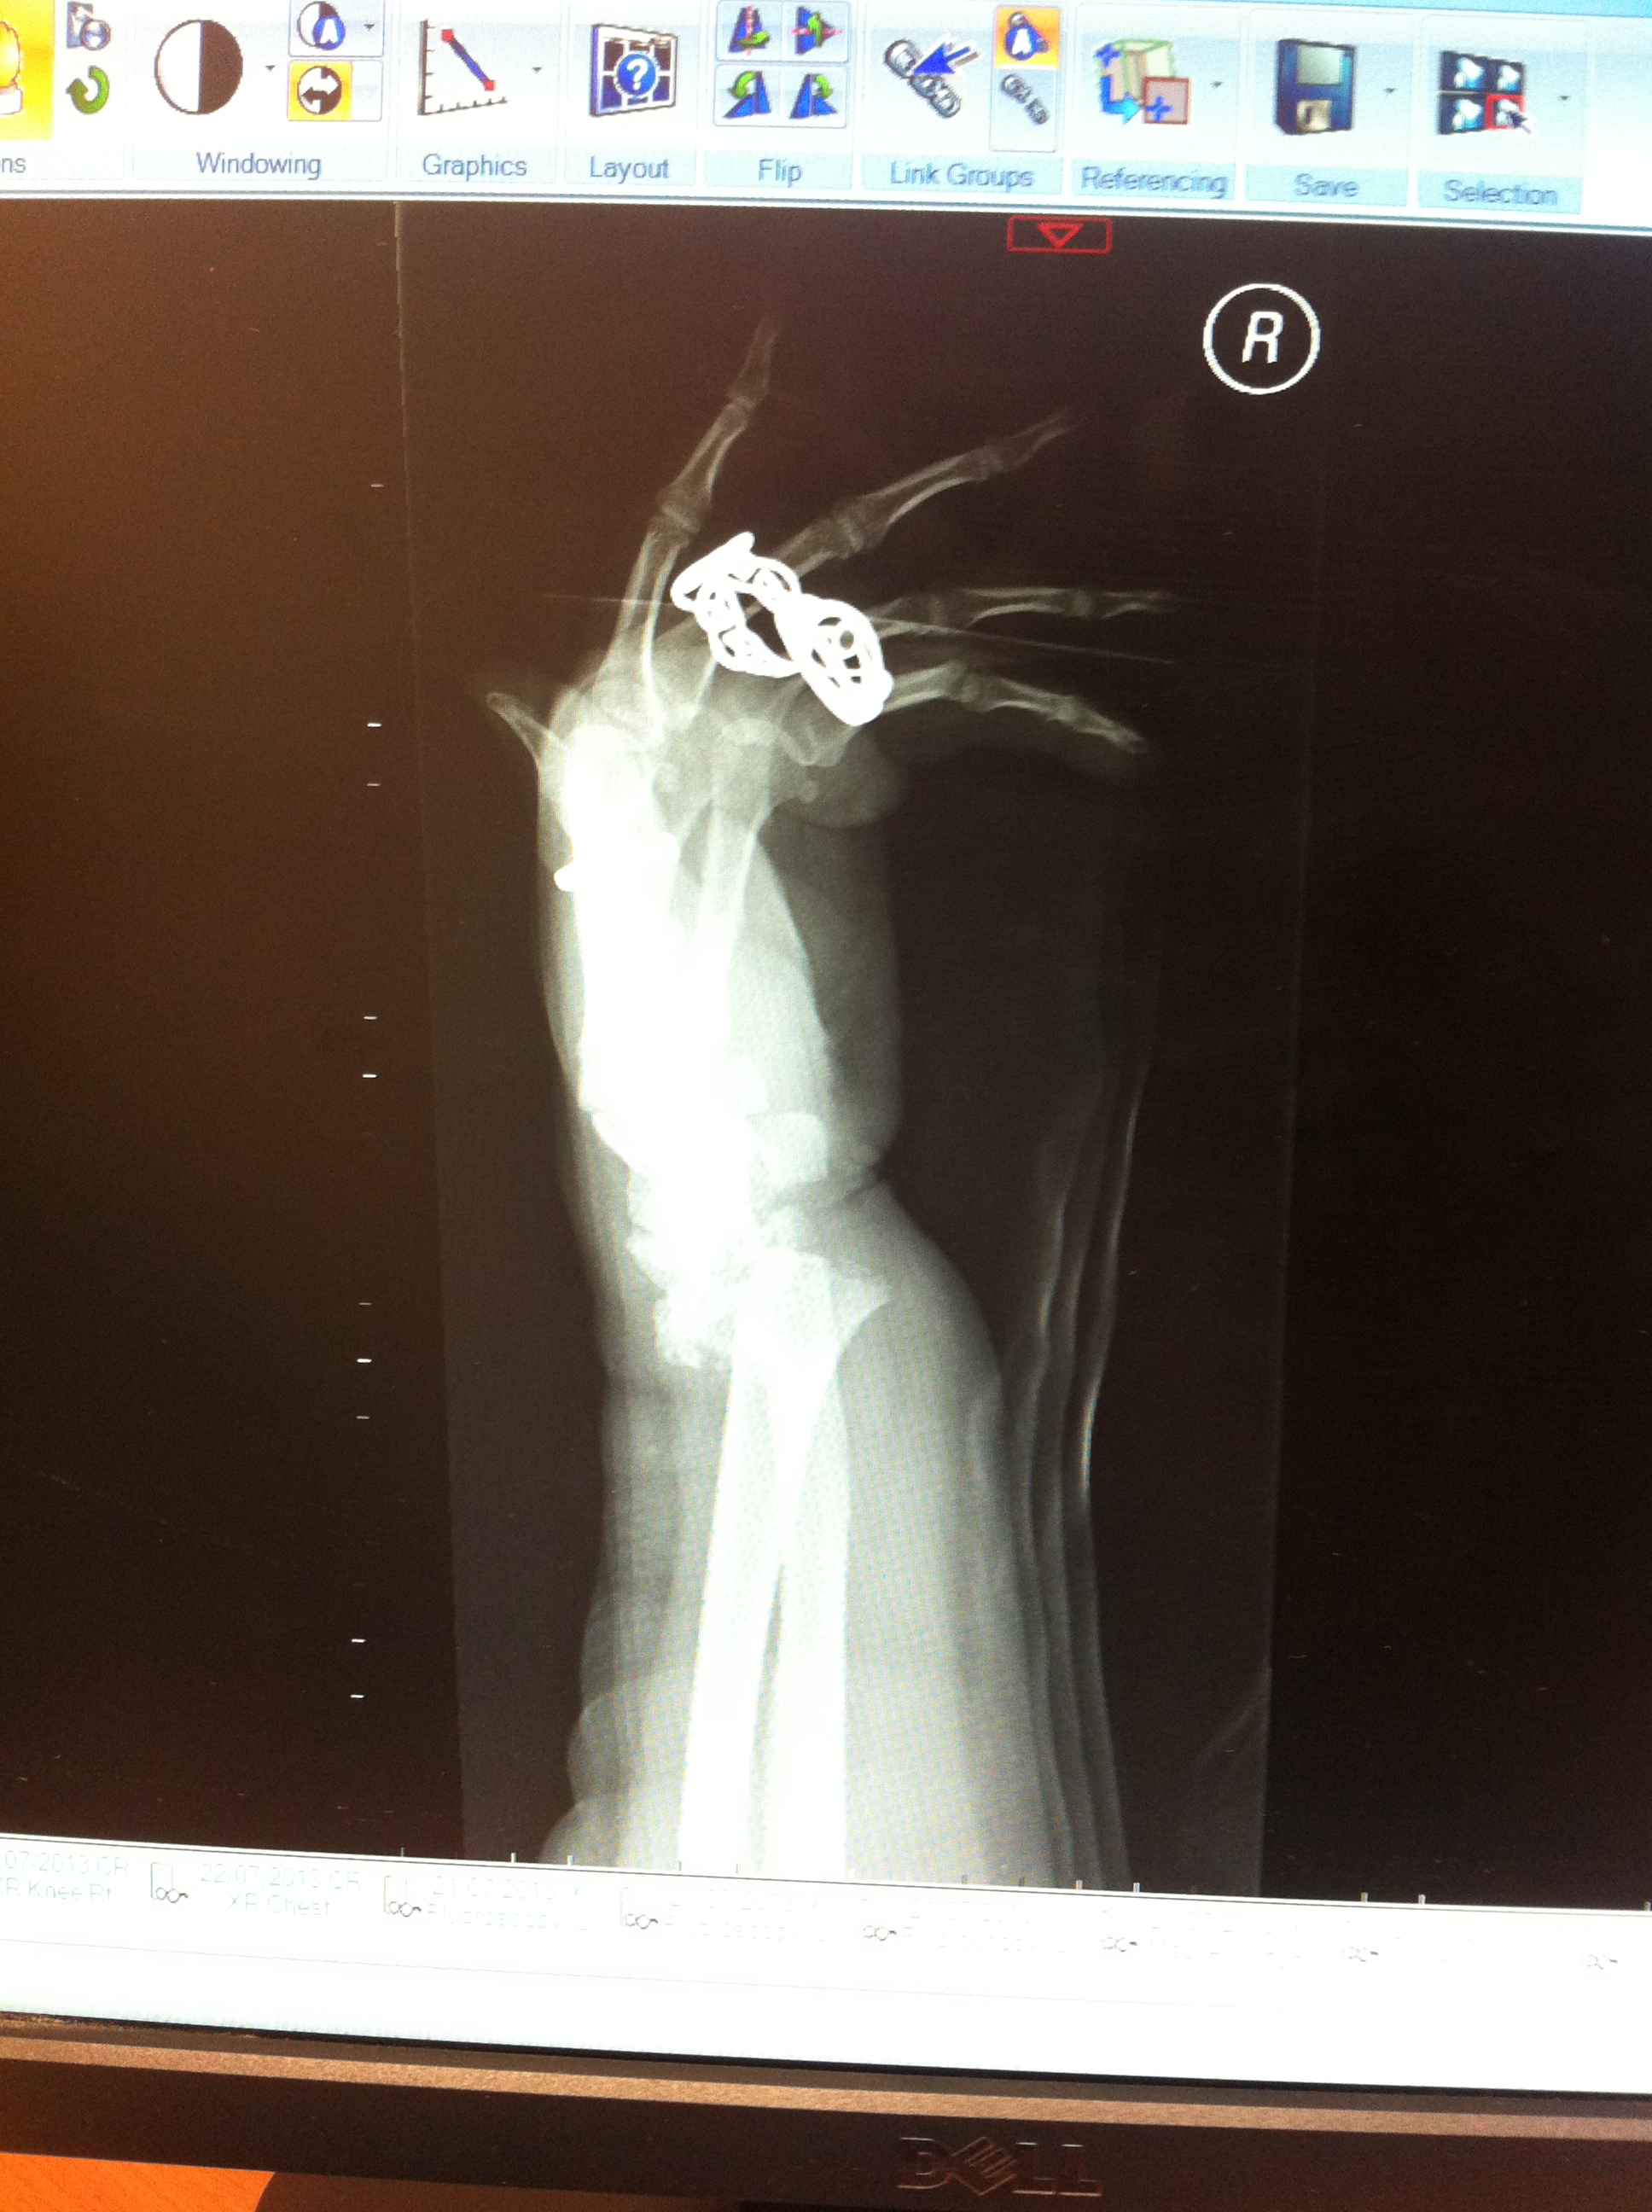

When I first came home, I was all fired up for doing EVERYTHING. All at once. I went in to work for a celebrity appearance. I went and got my hair cut properly, and coloured. I had an appointment at the fracture clinic the Monday after coming home, so more x-rays. The healing was going well, lots of lovely new bone. There was some talk of possibly loosening the ex fix at the next appointment (6 weeks on). And it was at this appointment that I got to see original x-rays (and some pics of them)….

Wrist (obviously!)

Pretty impressive collection of fractures – never bothered seeing the rib ones. Ok, 10 of them were smashed, but I figure that I’m not going to see that much that clearly.

Finally seeing the original x -rays has made me realise how bad my fractures actually were. It still sounds bonkers when I say it, but, in my head, I wasn’t that poorly.